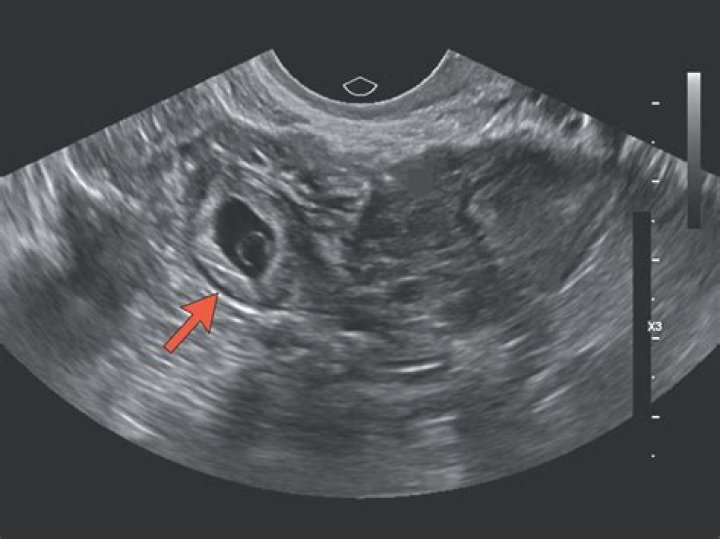

An ectopic pregnancy is usually diagnosed by carrying out a transvaginal ultrasound scan.

Can you see an ectopic pregnancy on ultrasound at 6 weeks?

An intra-uterine pregnancy can usually be seen by 5-6 weeks gestation or when the HCG level is more than 1000 IU/l. In 95% of ectopic pregnancy cases, a good transvaginal ultrasound examination can actually image the ectopic pregnancy in the Fallopian tube.

An ectopic pregnancy can be suspected if the transvaginal ultrasound examination does not detect an intrauterine gestational sac when the β-hCG level is higher than 1,500 mIU per mL.